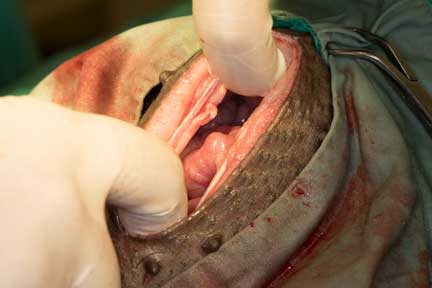

Once into the abdomen the large amount of intestines pop out through the incision. We were’t kidding when we said they had lots of intestines!

Somewhere in all of those intestines is the ovary, which our surgeon has identified

You can see the follicles on it as Dr. R clamps it for removal